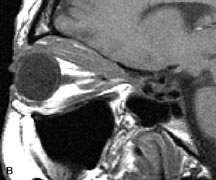

MRI is particularly helpful in the detection and characterization of subperiosteal hematomas of the orbit (Fig. 19). They are most commonly seen in the subperiosteal space of the superior orbit as well-defined masses following a traumatic injury. The signal intensity varies depending on the acute, subacute, or chronic nature of the hematoma, based on the stage of blood degradation. Fresh hemorrhages are hypointense on T1-weighted images and hyperintense on T2 images. Hematomas that are 1 to 7 days old are hypointense on both T1- and T2-weighted images. T1-weighted images of hematomas more than a week old are hyperintense due to the oxidation of deoxyhemoglobin to methemoglobin, whereas the T2 images remain hypointense.63

Fig. 19. A. T1- and (B) T2-weighted MR scans demonstrate a large acute subperiosteal hematoma (H) that lies between the cortical bone of the orbital roof and the inferiorly displaced periorthira (double arrow). The extracopal fat (arrow) and levator muscle are displaced inferiorly.